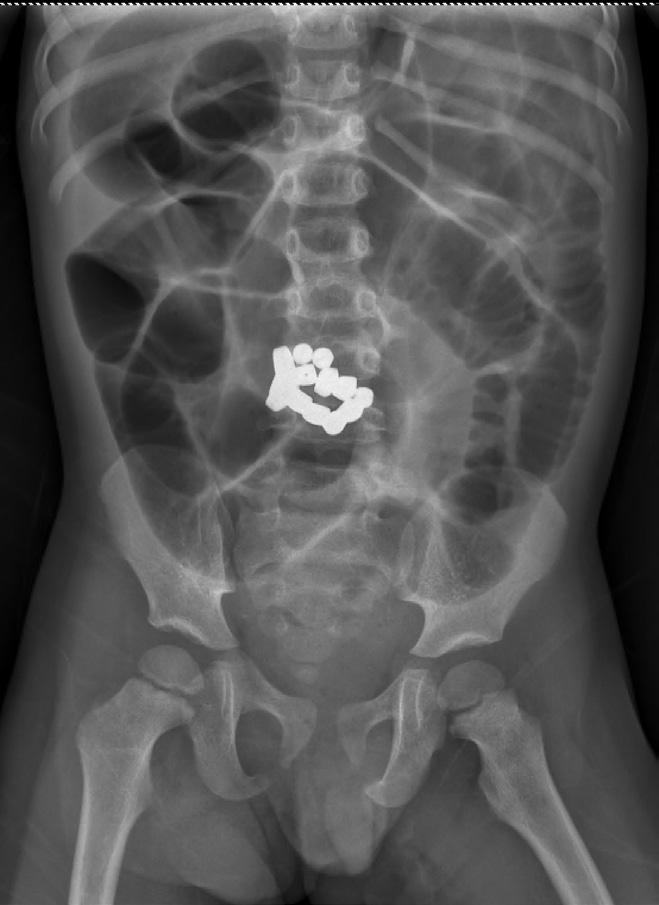

Dans le cas des aimants multiples, les complications proviennent de l’attraction entre les aimants et potentiellement d’autres objets métalliques à travers les tissus intestinaux. Cela peut entraîner des nécroses de pression, des obstructions, des fistules et des perforations digestives. Dans de rares cas, cela peut conduire à la mort. Les aimants à base de terre rare (ou néodyme) sont particulièrement associés aux complications; ils ont un pouvoir d’attraction plus de cinq fois supérieur à celui des aimants traditionnels9 .

5INGESTION D'AIMANTS

MULTIPLES 6 LONGUE VIS DE 5 CM DANS

L’ANTRE INGÉRÉE PAR UN

GARÇON DE 5 ANS

Les aimants

L’ingestion d’aimants tire sa gravité dans la nature et le nombre d’objets ingérés. Les aimants de jouets ou de réfrigérateurs lorsqu’ils sont ingérés de façon isolée ne représentent pas un risque majeur. Toutefois, lorsque les aimants sont ingérés en grande quantité (≥ 2) ou que les aimants sont fabriqués à partir de terres rares (néodyme) leur puissance d’attraction très élevée entraîne un risque de sténose et de nécrose intestinale majeur.

Dans ces situations, leur retrait s’impose lorsqu’ils se trouvent dans l’œsophage ou dans l’estomac. Si le corps étranger est déjà dans l’intestin grêle, un retour à domicile avec surveillance parentale est possible. Il faut néanmoins rester vigilant devant des symptômes tels les vomissements qui seraient le signe d’une sténose liée à une compression de l’intestin grêle (figure 5).